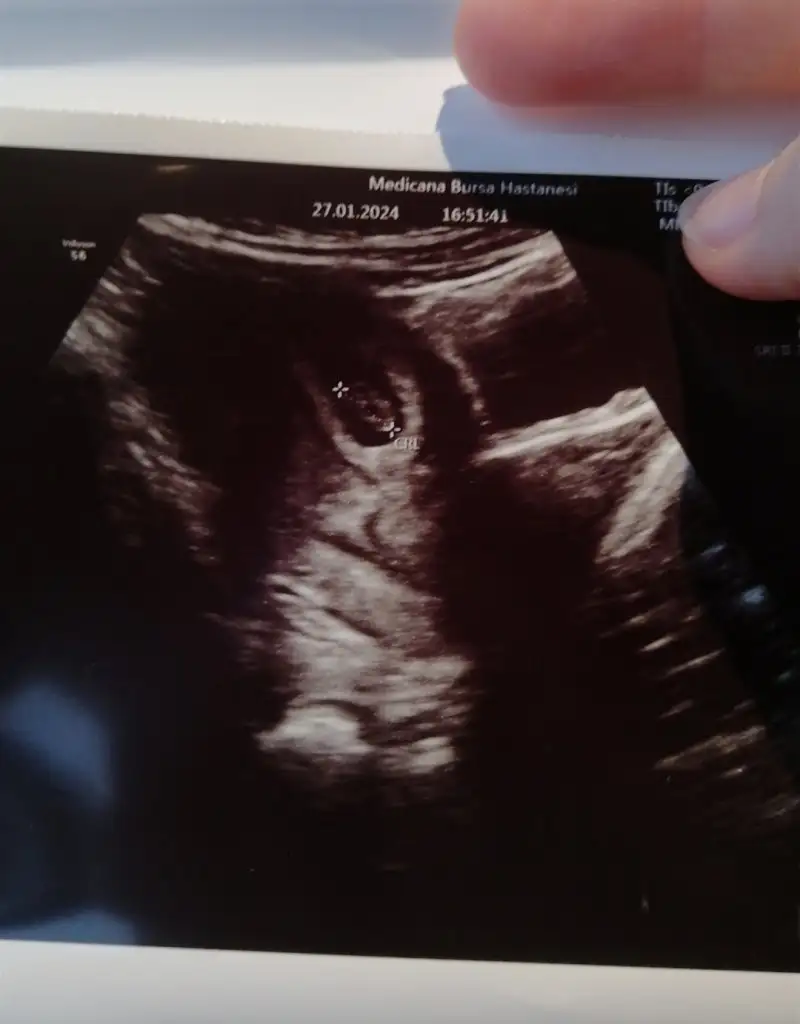

Hepinizden Allah razı olsun Rabbim inşallah sizlere nasip etsin saglilica kucağınıza almayı. Çok ağladım cok üzüldüm çünkü ilk gebeligimdi ve uzun zamandır istiyorduk. Akşam 5 te 1 damla bile diyemeyecegim bi leke gördüm takip ediyim dedim 7 de peçeteye silince akıntıyla kahverengi bisey geldi düşük değil ama kanlı akıntı. Hemen hastaneye gittik doktor 1-2 gün olmuş kalbi duralı dedi. Yarın sabah kürtaj için yatış olucak hala içimde duruyor minigim bi mucize olmasını bile dusunuyorum sabaha kadar kalbi donermi diye.

Ilk gittigim doktor kalp sesi gelmiyo ama kalbi atiyor dedi cihaz eski dedi. Kalp atışını duymadan gitmem dedim alttan bakalım dedi baktı ve yok dedi. Ben orda tamam diyip çıksam oylece beklicem 12. Haftaya kadar :KK43: sonra emin olmadim baska hastanye gittim orada da aynı cevabı aldım malesef.